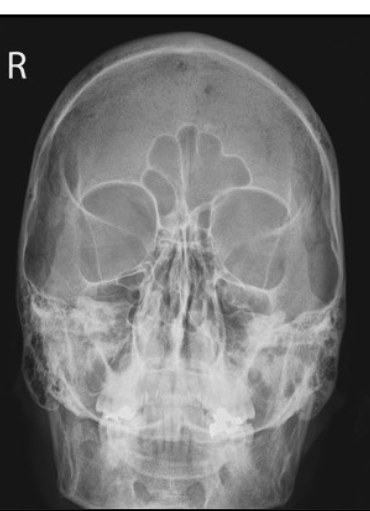

Q

nothing!

what are the corrections for this PA caldwell (3)

CP needs to be raised

nose to go right slightly

vertex to go left